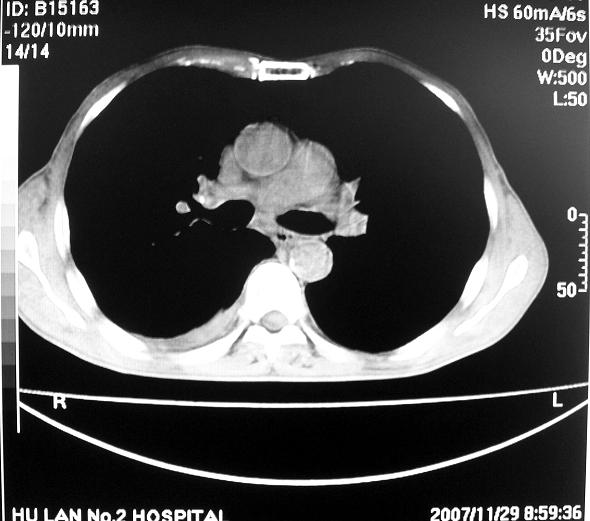

男63岁胸痛来诊

右下肺周围性肺ca并双肺及右侧胸膜转移。[emb6]

右肺病灶前缘不平整,略呈分叶状,其后方胸膜下脂线消失且似有向胸壁浸犯,左下肺球形灶内可见不规则空洞影,余双肺内可见多枚结节影,结合病史支持考虑肺癌肺内转移胸膜转移,便双肺后部病灶倒也是结核好发区域,建议穿刺活检

右下肺周围性肺ca并双肺及右侧胸膜转移。支持

右下肺周围性肺ca并双肺及右侧胸膜转移。

右下肺周围性肺ca并双肺及右侧胸膜转移。单看病变像炎性假瘤。

右下肺癌,双肺及胸膜转移

右下肺癌伴双肺及胸膜转移。

[quote]以下是引用余辉在2007-12-2 20:29:00的发言:[br]右肺病灶前缘不平整,略呈分叶状,其后方胸膜下脂线消失且似有向胸壁浸犯,左下肺球形灶内可见不规则空洞影,余双肺内可见多枚结节影,结合病史支持考虑肺癌肺内转移胸膜转移。

左肺病灶内可见空泡征及典型的胸膜牵拉征,不排除原发周围型肺癌的可能.